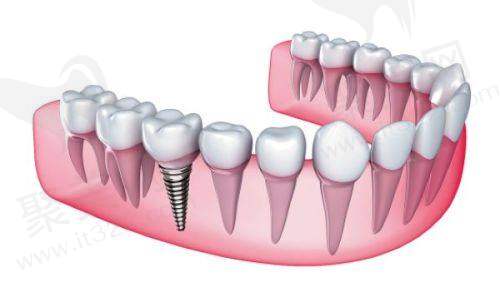

普通种植:就是拔牙后等伤口愈合再进行种植,这种方式费用相对较低,大概在 5000 - 15000 元。

(一)种植手术费

种植手术费大概在 2000 - 4000 元,这其中包含了麻醉、手术操作等费用。

(二)牙冠费用

烤瓷牙冠:价格在 800 - 2500 元,性价比高,里面含有金属基底。

全瓷牙冠:费用在 2500 - 8000 元,美观自然,不会引起金属过敏。